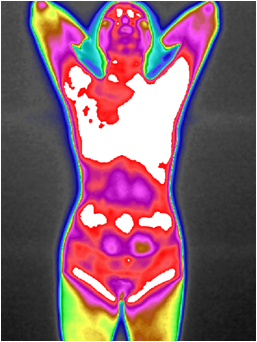

图5 子宫肌瘤红外热成像图

图6 肺癌预警红外热成像图